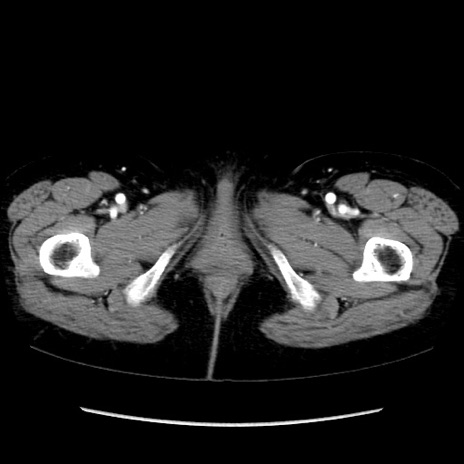

症例32(横断像)

【症例】40歳代 女性

【主訴】上腹部痛、嘔気・嘔吐

【現病歴】約9時間前頃から急に上腹部痛、嘔気、嘔吐が出現。改善しないため救急要請。

【既往歴】子宮頚癌(広汎子宮全摘術、放射線療法)、腸閉塞

【身体所見】腹部:平坦、軟、腸雑音亢進、上腹部を中心に腹部全体に圧痛あり。

【データ】WBC 8400、CRP 0.03